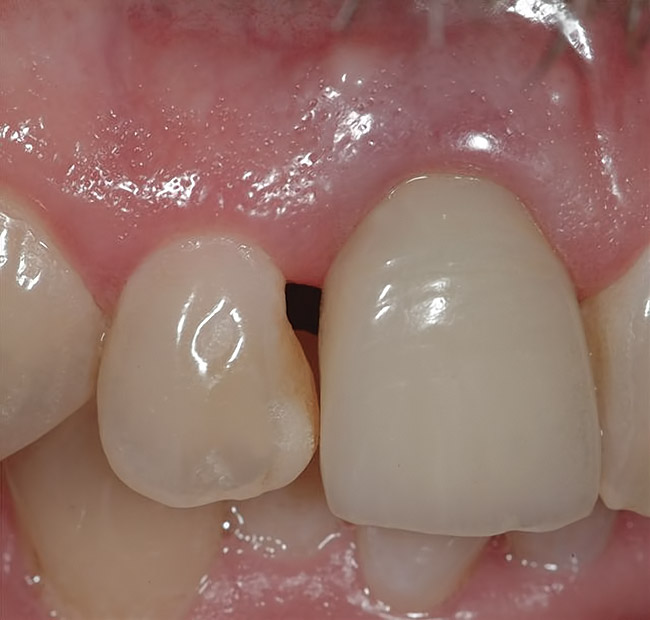

Figure 4  Characterization of the interproximal bone and tooth contacts: A periapical radiograph assists in measuring the distance from bone crest to the adjacent tooth contact points for missing tooth No. 8. The mesial bone crest to the adjacent tooth contact distance is < 5 mm, while the distal bone crest to adjacent tooth contact distance is > 6 mm (Fig 4). One-year following implant placement, conservation of these dimensions is revealed (Fig 5). The clinical photograph (Fig 6) of the lateral incisor adjacent to tooth No. 8 implant crown demonstrates that the absence of distal interproximal (papilla) fill related to the observed bone crest to contact distance exceeds 6 mm.

Figure 4

Figure 5  Characterization of the interproximal bone and tooth contacts: A periapical radiograph assists in measuring the distance from bone crest to the adjacent tooth contact points for missing tooth No. 8. The mesial bone crest to the adjacent tooth contact distance is < 5 mm, while the distal bone crest to adjacent tooth contact distance is > 6 mm (Fig 4). One-year following implant placement, conservation of these dimensions is revealed (Fig 5). The clinical photograph (Fig 6) of the lateral incisor adjacent to tooth No. 8 implant crown demonstrates that the absence of distal interproximal (papilla) fill related to the observed bone crest to contact distance exceeds 6 mm.

Figure 5

Figure 6  Characterization of the interproximal bone and tooth contacts: A periapical radiograph assists in measuring the distance from bone crest to the adjacent tooth contact points for missing tooth No. 8. The mesial bone crest to the adjacent tooth contact distance is < 5 mm, while the distal bone crest to adjacent tooth contact distance is > 6 mm (Fig 4). One-year following implant placement, conservation of these dimensions is revealed (Fig 5). The clinical photograph (Fig 6) of the lateral incisor adjacent to tooth No. 8 implant crown demonstrates that the absence of distal interproximal (papilla) fill related to the observed bone crest to contact distance exceeds 6 mm.

Figure 6

Additional attention must be paid to the osseous architecture related to the adjacent teeth, as this controls interproximal tissue form.7 The crest of healthy bone is 4.5 mm to 5 mm from the contact point between anterior teeth8; a similar 5-mm distance from the contact point to the bone crest has been measured between an implant and natural tooth. An important and additional rule to guide esthetic implant outcomes is that the adjacent tooth should possess interproximal bone levels no further than 6 mm from the natural tooth contact point (Figure 4 through Figure 6). While the ideal distance is justifiably indicated to be 5 mm, this 6-mm rule establishes a point at which marked interproximal tissue deficiencies and asymmetry will not be overcome.